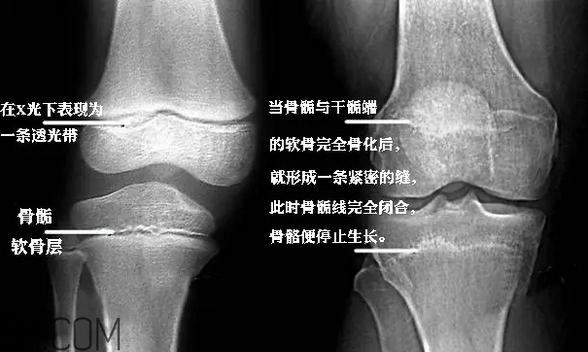

“骨骺”是兒童出生后在不同時間內(nèi)出現(xiàn)的二次骨化中心,通俗一點就是骨骼的生長點。

適量的運動會刺激生長點,促進孩子的生長發(fā)育。

但是運動量過大時,就會造成慢性疲勞,損傷到骨骺,就會影響到孩子的生長發(fā)育了。